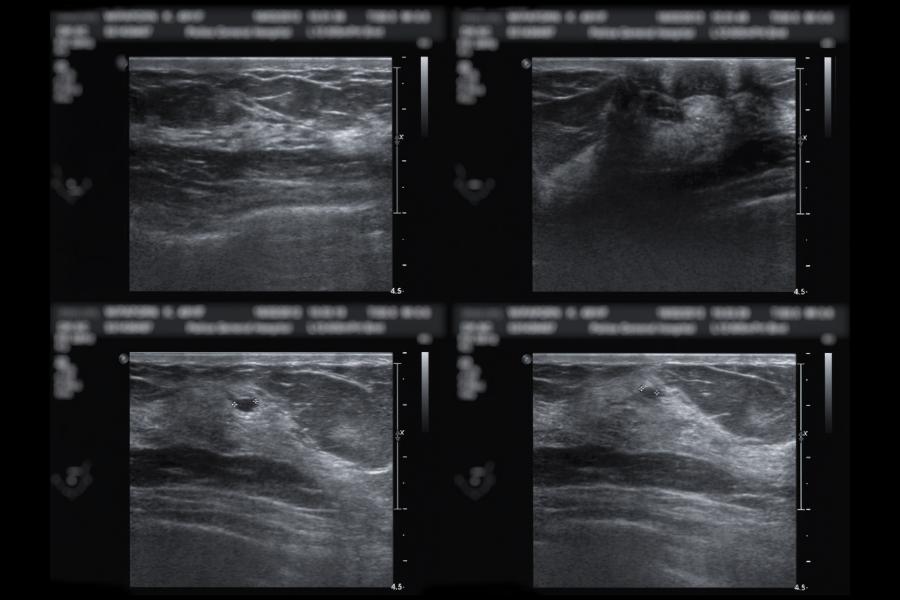

Image caption: Conventional ultrasound of breast tissue compared to the new method

Image credit: Johns Hopkins University

Ultrasound works by sending sound waves through a probe into the breast. The sound bounces off of structures like masses and is recorded. When it works perfectly, the sound travels directly from the mass right back to the probe. But with dense breast tissue, the sound scatters before it reaches the mass, causing "acoustic clutter" in the image. A benign liquid-filled cyst which should appear black in images will often look gray inside, which is how a cancerous growth would look.

The new method changes nothing with ultrasound production, but improves on how the signals are processed. Conventional ultrasound relies on the amplitude of signals, turning high and low signals into blacks, whites, or grays. The new method is "coherence-based," meaning the image relies on how similar signals are to neighboring signals.